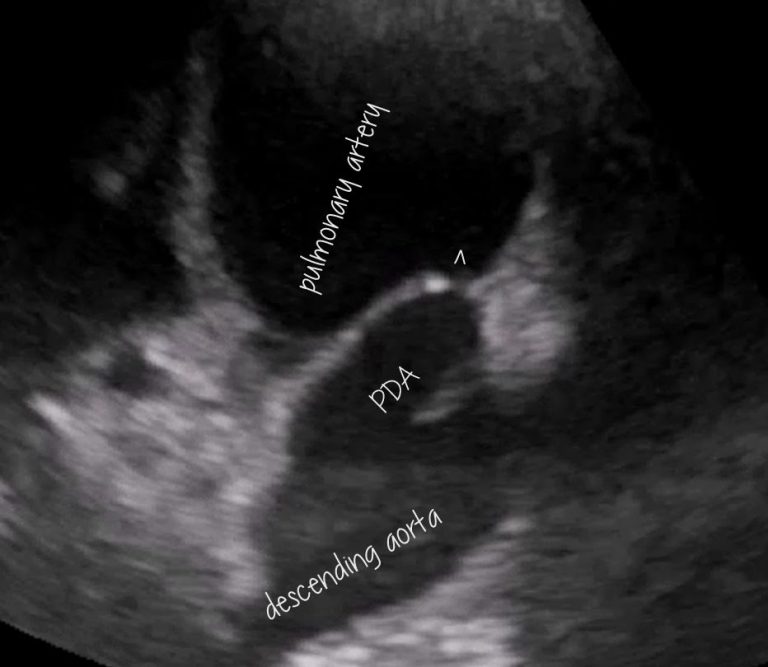

From www.vetpracticesupport.com

Canine patent ductus arteriosus (PDA) echocardiography Vet Practice What Is A Pda In A Dog Failure to identify and close a pda can result in. Patent ductus arteriosus (pda) is a common form of congenital heart disease in dogs (schrope, 2015; Patent ductus arteriosus (pda) is the second most common congenital heart defect in dogs. Technically, the problem arises when. Sometimes, the condition is also referred to as pda. Patent ductus arteriosus (pda) is one. What Is A Pda In A Dog.